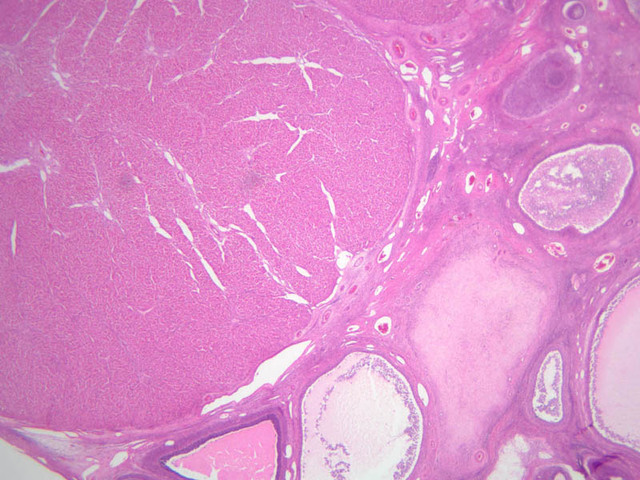

Mammary Gland

The resting or inactive mammary gland consists of predominantly dense connective tissue with small clusters of ducts and a few glandular elements (slide A-93 [2.5x-labeled, 10x, 20x, 40x] [1x, 2.5x, 10x, 20x]). It is difficult to differentiate between small ducts and alveoli as each is lined by simple low cuboidal cells. Lobes and lobules are not well defined. During puberty, predominantly under the influence of the ovarian hormone estrogen, the glandular or epithelial ducts proliferate and begin to differentiate into clusters of ductal and alveolar units termed terminal ductal lobule units (TDLUs). The non-pregnant gland will form multiple TDLUs that will not fully differentiate until pregnancy-induced growth. TDLUs are classified into Type I, Type II and Type III based on density of the ductules within each lobular unit. Type I and Type II lobules are typical of inactive glands that have not undergone a pregnancy cycle. Type III lobules are seen only in active glands or in inactive glands that have been through a pregnancy. Intralobular connective tissue is loose connective tissue that surrounds the alveoli and ducts within a lobule. The interlobular connective tissue is dense and contains considerable adipose tissue.

During pregnancy, predominantly under the influence of the ovarian hormone progesterone and the pituitary hormone prolactin, the glandular elements proliferate and differentiate to form milk-secreting units. In later stages of pregnancy, alveolar development becomes prominent and the amount of connective tissue and adipose tissue decreases. The secretory cells hypertrophy and accumulate secretory product.

The mammary gland in its active state is a compound tubuloalveolar gland (slide A-92 [10x, 20x, 40x-labeled] [2.5x, 10x, 20x, 40x]; A-94 [2.5x, 10x, 20x, 40x]). At this time, the gland is predominantly glandular tissue. Each alveolus is lined by a simple cuboidal epithelium. At the base of these cells, and within the alveolar basal lamina, are the stellate-shaped myoepithelial cells that are highly contractile and function to facilitate milk ejection.